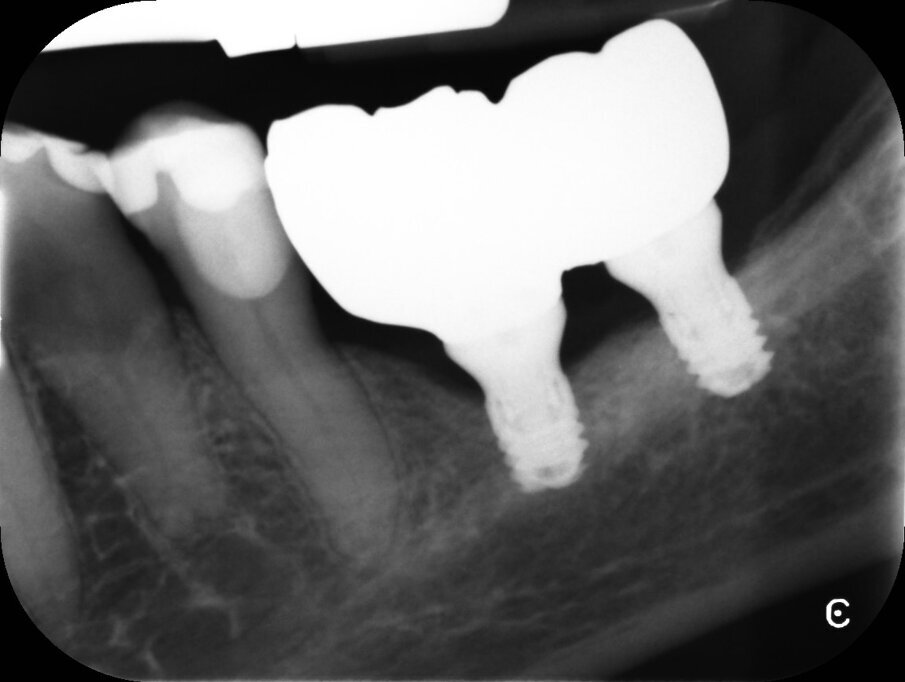

Fase protesica

Dopo tre settimane i tessuti attorno agli impianti apparivano sani e privi di infiammazione. Era presente anche una banda di tessuto cheratinizzato. Fu presa un’impronta con tecnica del cucchiaio aperto e due settimane dopo furono consegnate due corone in zirconio avvitate. Il controllo radiografico evidenziava una buona stabilità dell’osso crestale (Figg. 10-13).